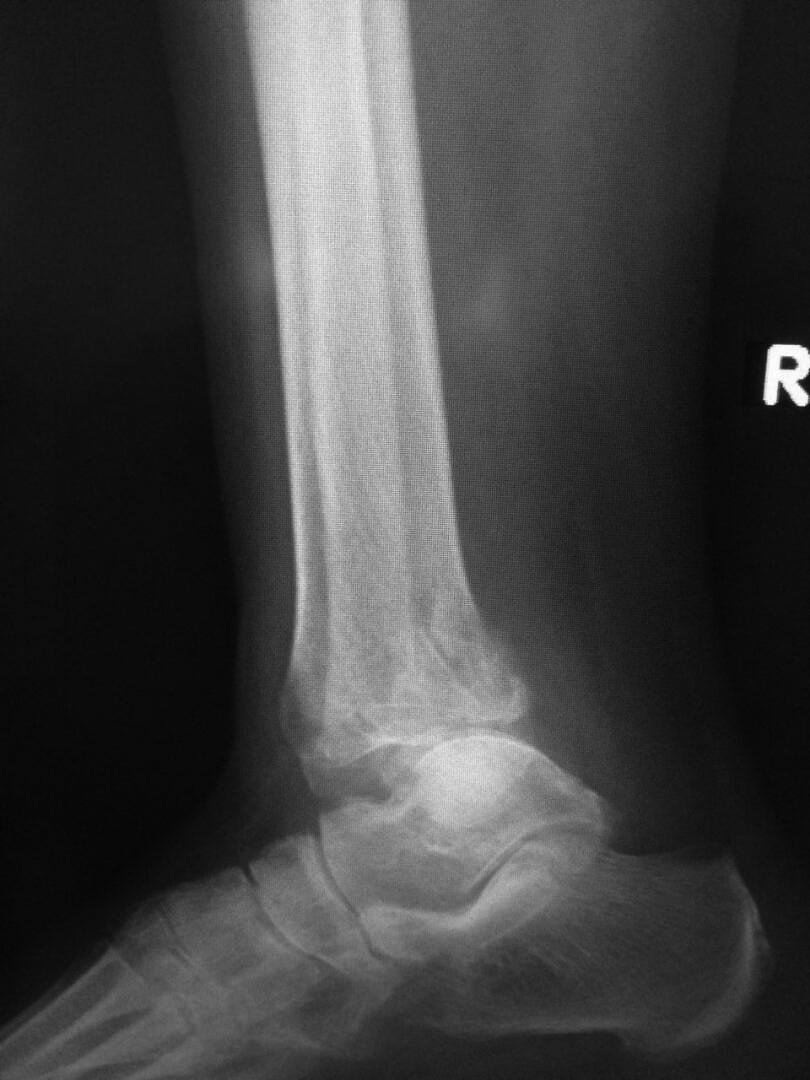

Пациентка 60л. 3 месяц назад получила травму г/стоп сустава: перелом

обеих лодыжек, заднего края с подвывыхом стопы. Нигде не лечилась. Мне

пригласили на консультацию в другую обл.  Все идет к артродезу. У нее